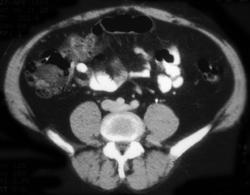

Pelvic Abscesses S/P Colon Resection